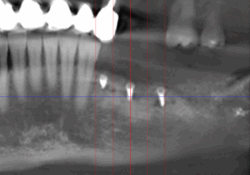

Lorsque l’os de la mâchoire est insuffisant pour soutenir un implant dentaire, des techniques de reconstruction osseuse peuvent être nécessaires. Ces procédures permettent d’augmenter le volume osseux pour garantir la stabilité de l’implant.

- Greffe osseuse : Ajout d’os ou de matériaux pour augmenter le volume osseux.

- Régénération Osseuse Guidée : Stimule la repousse osseuse grâce à des biomatériaux.

- Sinus Lift : Augmentation de l’os dans la région des molaires supérieures par élévation des sinus.